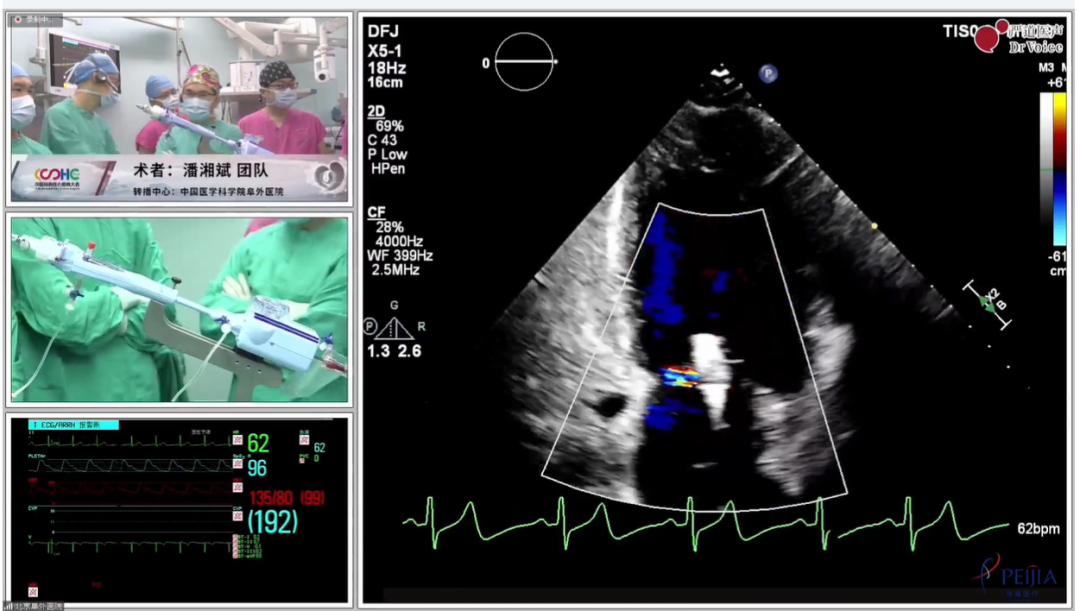

2023年3月30日,在第四届中国结构性心脏病大会暨第三届卵圆孔未闭规范化诊疗研讨会上,中国医学科学院阜外医院潘湘斌教授团队成功完成局麻下单纯经胸超声引导(TTE)MitraClip™手术。手术中采用团队自主研发的超声引导专用介入引导导丝,全程仅使用经胸超声作为唯一影像引导手段,手术效果良好,术后即刻二尖瓣反流降至微量。来自美国、德国、意大利、波兰等国家的专家们线上观看了手术全过程,对本次手术表示惊叹,称赞中国TEER技术取得了新的突破。

患者为高龄男性,年龄82岁。术前超声心动图诊断为重度退行性二尖瓣反流(MR 4+),反流位于2区,后叶P2区脱垂合并腱索断裂,多普勒检查可见大量偏心性反流。心脏团队评估该患者为外科高风险患者,考虑使用MitraClip™进行经导管二尖瓣缘对缘治疗,因患者有食道狭窄病史,经术前讨论评估,决定为该患者行单纯经胸超声(TTE)引导下MitraClip™手术。

手术过程

在房间隔穿刺时,手术团队使用自主研发的超声引导专用介入导丝,该导丝头端呈纺锤形,在TTE下清晰可见,精准定位房间隔穿刺部位,波兰Zenon Hucze等专家给予了高度评价。